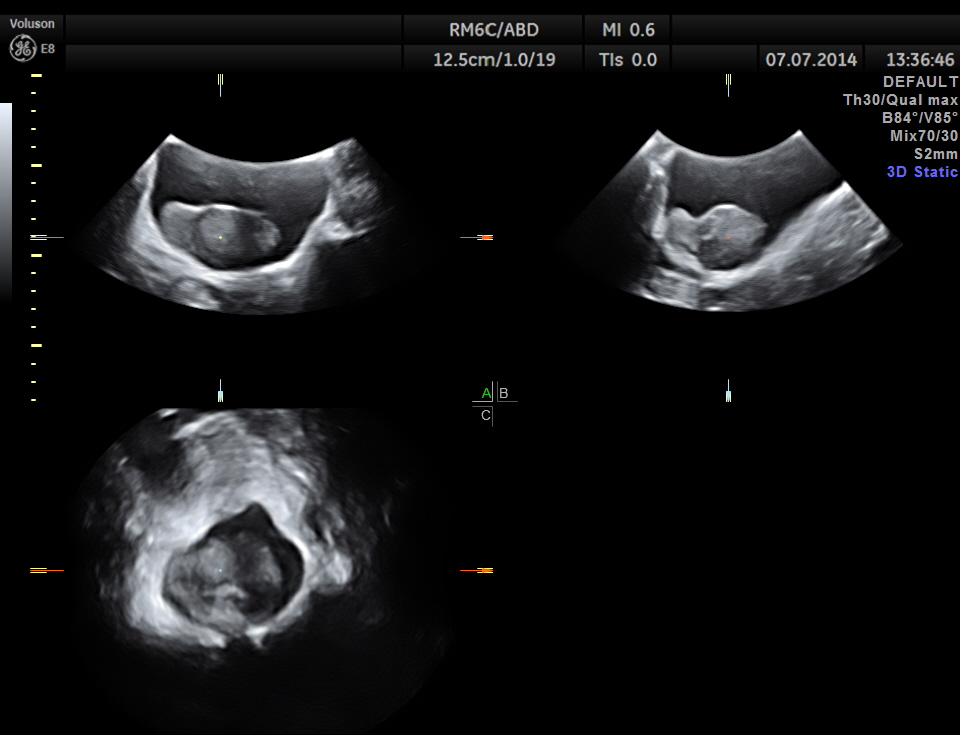

The right kidney is shown below. A solid mass is seen in the lower pole region.

The mass measurements are given below.

GLASS BODY RECONSTRUCTION shows increased vascularity.

The diagnosis offered was HYPERNEPHROMA ( RENAL CELL CARCINOMA )

In this patient the increased vascularity is brought out very well by glass body imaging . Clots of blood seen in the urinary bladder gave the false impression of a mass lesion in the bladder initially.The importance of a dynamic study of turning the patient to the sides should always be remembered.